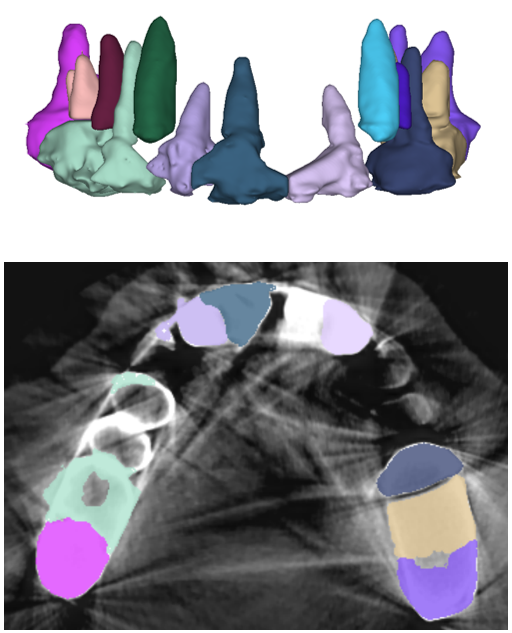

The manual seeded level-set methods [6, 7] demonstrate inferior performances while segmenting teeth with predominant metal artifacts (Table II). The energy-based (i.e., level-set function) algorithmic approach failed while defining an optimum stopping criterion (Fig. 12b). The AJI measures for level-set methods are omitted because the box detectors do not exist in the level-set-based methods. In particular, the low precision and sensitivity values indicate that level-set methods have over-segmented or under-segmented the teeth in many cases (Figs. 12b and 13a). The accuracies of the Mask-RCNN [17] and ToothNet [11] showed comparable performance to the level-set-based methods. The instance segmentation framework successfully detected and segmented the teeth automatically. However, it failed to detect all the teeth regions accurately, which resulted in a degradation of the segmentation performance. Moreover, the performance of the segmentation itself also showed low accuracy owing to the metal artifacts (Figs. 12c and 12d). Figure 13 illustrates the more severe conditions of metal artifacts. The performance of the detection and segmentation processes significantly degraded in ToothNet [11] (Fig. 13b) and Mask-RCNN [17] (Fig. 13c). Conversely, our proposed method outperformed the other state-of-the-art methods (Figs. 12e and 13d); further, the comparison between the PA- and non-PA-based results also demonstrated that the employment of a PA detector significantly improved the proposed architecture (Table II). The superior AJI value clearly shows that successful detection improved the overall performance.

Table III shows that our proposed TSNet is superior to other networks in a stand-alone segmentation performance (i.e., using the ground-truth boxes). Moreover, the overall performance of the networks that utilized PA-based ground-truth (PAGT) showed better accuracy than the ones that used the original image axes. The original 3D U-net [26] and others failed to segment the teeth with metal artifacts (Figs. 14 and 15). The DenseVNet [35] showed relatively higher precision than the 3D U-net [26] and VoxResNet [27] as DenseVNet employed a shape-prior based on trainable parameters [35]. The trained shape-prior based on well-bounded images suppressed the false positive responses. However, DenseVNet demonstrated inaccurate segmentation (i.e., sensitivity) due to the large shape variance of teeth.

We extended the evaluation of segmentation network with the following variants (Table V): TSNet-C, TSNet-D, and TSNet-CD, which represent without cutout augmentation, without distance loss (3), and without both the cutout and the distance loss (i.e., 3D U-net [26] with SkipBlocks), respectively. We used the dice loss in TSNet-D and TSNet-CD. The result shows that the distance loss metric was the primary factor to achieve success in the individual tooth segmentation. Figure 14 illustrates the box plots of the PAGT-based results and the ablations (Tables III and V) of the proposed network; further, Fig. 15 illustrates that the proposed TSNet is superior to other methods.